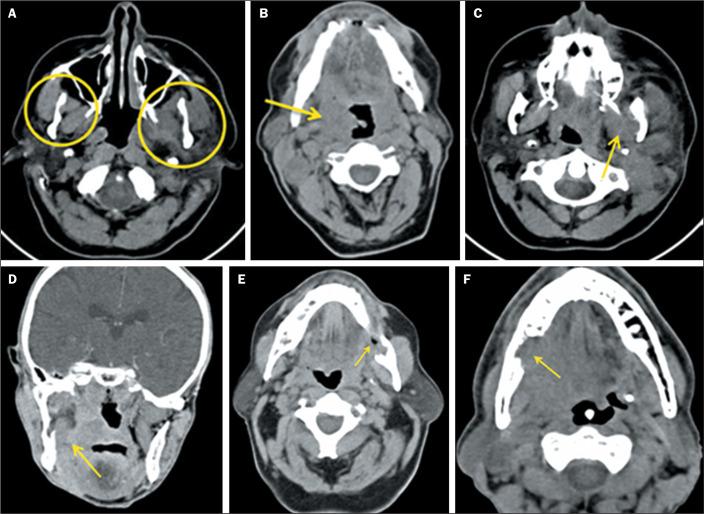

We evaluated the medical records of 65 patients with malignant tumors in the regions described. The images were analyzed by two physician examiners, working independently, who were blinded to the clinical data. In the evaluation of the masticator space, the following parameters were considered: symmetry with the contralateral space; obliteration of the fat plane, retromolar trigone, or pharyngeal space; edema/atrophy of the medial or lateral pterygoid muscles; and destruction of the mandibular ramus.

Obliteration of the fat plane was found in 69.2% of the patients. Asymmetry, edema/atrophy, and bone destruction were detected in 27.7%, 26.2%, and 20.0% of the patients, respectively. Trismus was identified in 15.4% of the patients. Of the patients with trismus, 90.0% had stage T4 tumors, compared with only 43.8% of those without trismus. Trismus was 11.6 times more common among the patients with stage T4 tumors than among those with lower-stage tumors. Neoplasms of the tonsillar fossa and retromolar trigone collectively accounted for 95.0% of the cases. The CT scans showed edema/atrophy of the pterygoid muscles in 60.0% of the patients with trismus and in 21.8% of those without. An association was observed between T4 tumor stage and edema/atrophy of the pterygoid muscles. In addition, the risk of trismus was 5.4 times higher among the patients with stage T4 tumors.

In our patient sample, the most common finding was obliteration of the fat plane, followed by asymmetry and edema/atrophy. Most of the patients with T4 tumors had trismus, together with edema/atrophy of the pterygoid muscles.